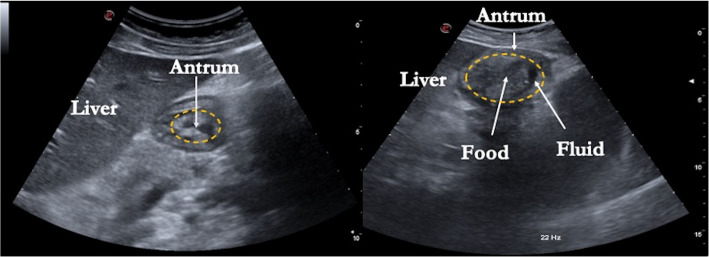

胰高血糖素样肽-1受体激动剂是一类模仿肠道在饭后释放的天然肠促胰岛素激素的药物,它们非常适合治疗2型糖尿病。胰高血糖素样肽-1受体激动剂也通过作用于大脑的食欲调节中心导致饱腹感和食欲减少,导致肥胖患者体重减轻。然而,由于胰高血糖素样肽-1受体激动剂的作用是减缓胃排空,在深度镇静或全身麻醉的患者中,对胃抽吸的安全性提出了担忧,并且考虑到它们在血液中的半衰期长,在围手术期难以控制。本综述的目的是:(i)探讨目前关于麻醉前误吸风险的知识;(ii)描述在手术前评估胃内液体和食物存在的方法;(三)平衡实际的警告与未来发现它们的好处的机会。

Glucagon-like peptide-1 receptor agonists are a class of drugs that mimic a natural incretin hormone released by the intestine after meals, and they are well-suited for treating type 2 diabetes. Glucagon-like peptide-1 receptor agonists also lead to satiety and appetite reduction through action on the brain's appetite regulation centers, leading to weight loss in obese patients. However, because glucagon-like peptide-1 receptor agonists work to slow gastric emptying, a safety concern has been raised in patients undergoing deep sedation or general anesthesia regarding gastric aspiration, and considering their long half-life in the blood, they are difficult to manage in the perioperative period. The purpose of this review is (i) to explore the present knowledge about the risk of aspiration before anesthesia; (ii) to describe the method for evaluating the presence of liquid and food in the stomach before surgery; and (iii) to balance the actual warning with the opportunity for future discovery about their benefits.